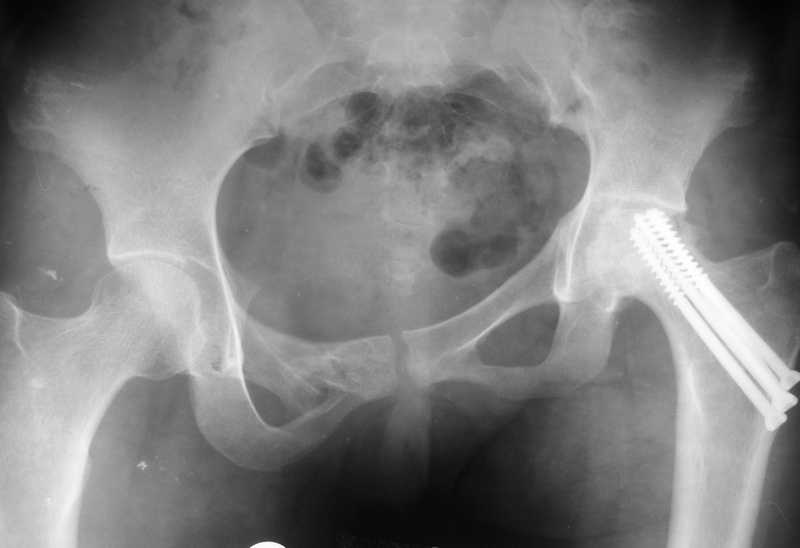

Привет всем. Укорочение за счет таза не менее 3см.

В задних отделах таза ничего не изменилось (см снимок в аппарате). Картинка кажется лучше за счет оссификата в седалищной вырезке от задней колонны к кп сочленению.

разговоров нет, смещение значимое, какое оно было, такое и осталось. Будут проблемы и с сидением и с осанкой и т.д. Идеальным вариантом было бы, конечно, исправить деформацию, а потом запротезировать. Но... цена вопроса. сейчас деформация, судя по костной мозоли, стабильная, и таз несет основную свою функцию - опорную, явно КПС не болит. Превратить стабильную деформацию в нестабильную и потом ее исправить - задача непростая, но выполнимая. Оперативное лечение будет сложное, скорее всего многоэтапное и длительное. С определенными рисками, общехирургическими и специфическими, например несращение зоны остеотомий - нестабильный таз, ризидуальное смещение (в пределах 1 см вполне вероятно). Если считать, что на тазе укорочение см 3, остальные 5. все-таки сгибательно-приводящая контрактура. На протезе от контрактуры можно избавиться, да и см 2 удлинить за счет опила, головки. В такой ситуации решение должна принять пациентка и оно должно быть действительно информированным.

Все-таки основное укорочение за счет таза-смещение дна вертлужной впадины вверх порядка 3 см., плюс разворот, дающий приводящую контрактуру и укорочение еще 3-4 см.

По первым снимкам имеется сложная травма с переломом ацетабулума (видна линия перелома в задней колонне) и таза с ипсилатеральным переломом шейки. Не удалось репонировать крестцово-подвздошное сочленение, и смещение с ротацией осталось, особенно в верхней ветви лонной кости. Клинические снимки подтверждают остаточную деформацию и укорочение конечности за счет таза.